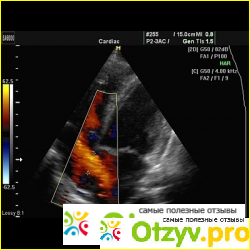

Ультразвуковое исследование сердца (УЗИ сердца) я проходила, будучи беременной. Это было в 2012 году, в январе, если не ошибаюсь. Просто началось с того, что терапевт обнаружил, когда слушал сердце, что у меня как-то там не так оно стучит =) Сначала отправила к кардиологу, он сказал, что возможно ВСД (она потом подтвердилась, но мне сказали, что при беременности, да и не только, такое бывает, и вообще с этим ходит чуть ли не каждый третий).

Кардиолог назначил кардиограмму и УЗИ сердца. Кардиограмму, кажется, делали бесплатно, а УЗИ - платно, и стоило оно в 2012 году 120 гривен, сейчас, наверное, еще дороже. Делала я в отделении "Соляриса". Делала мне его врач женщина. Я сняла свои вещи, легла на кушетку, и минут 10 мне делали это узи. Никакой боли или чего-то неприятного я не почувствовала. Мне сделали это УЗИ, дали листик бумаги, где всё описано. Сказали, что ничего плохого для беременности тут не обнаружено, то есть никаких угроз. Потом результаты я понесла кардиологу, он тоже сказал, что все нормально. В общем, кроме дороговизны (хотя, наверное, любое узи сердца не дешевое) я минусов не нашла. Ну и, кажется, говорят, что узи само по себе не очень полезное, а немного даже вредное.